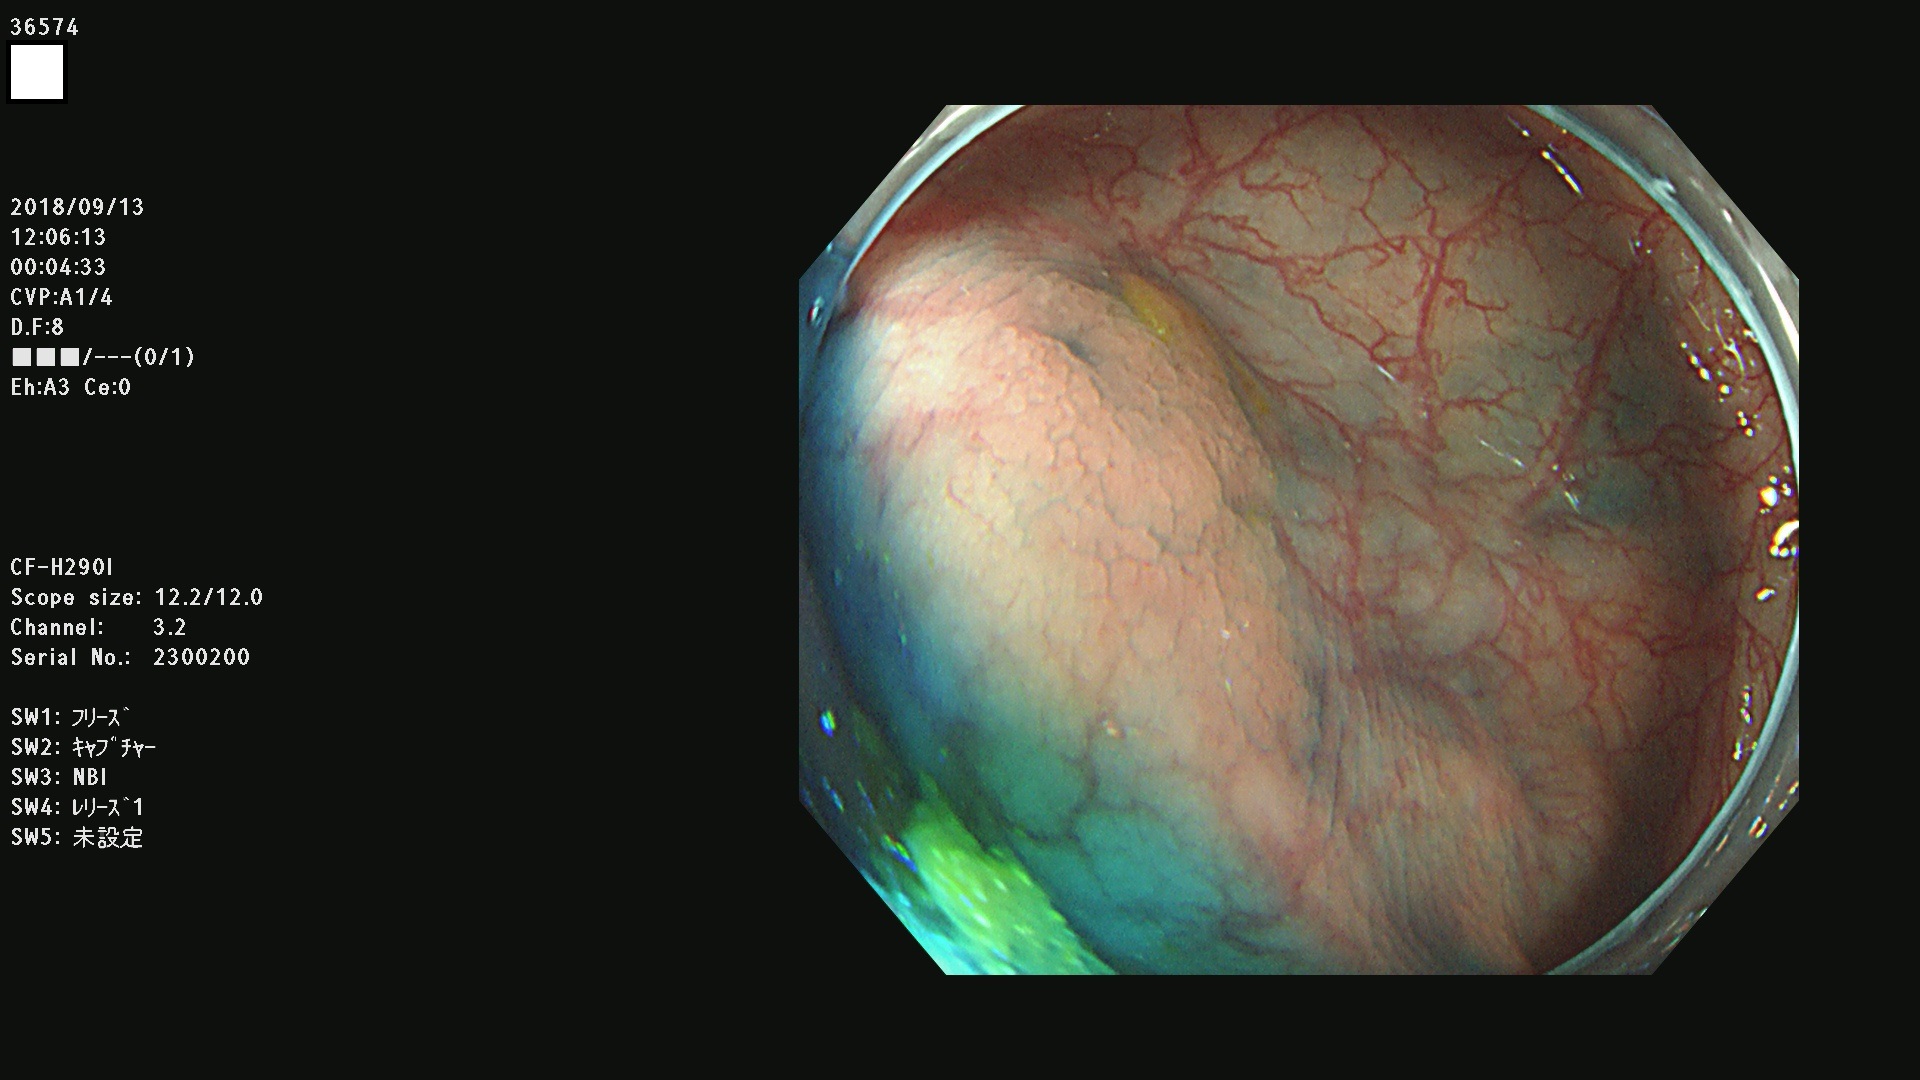

36500 36503 36504 36505 36507(SSAPのみ) 36508 36509 36510 36511 36514 36515 36517 36518 36520 36522(SSAPのみ) 36523 36524 36526 36528 36530 36531 36532 36533 36534 36535 36536 36538 36541 36542 36543 36544 36545 36546 36548 36550 36551 36554 36555 36556 36558 36559 36560 36561 36564 36565 36567 36568 36570 36572 36573 36574 36575 36576 36577 36578 36579 36580 36582 36584 36586 36591 36592 36593 36594 36595 36596 36597 36598

発見困難で危険性の高い平坦型病変(上記100名より抽出)